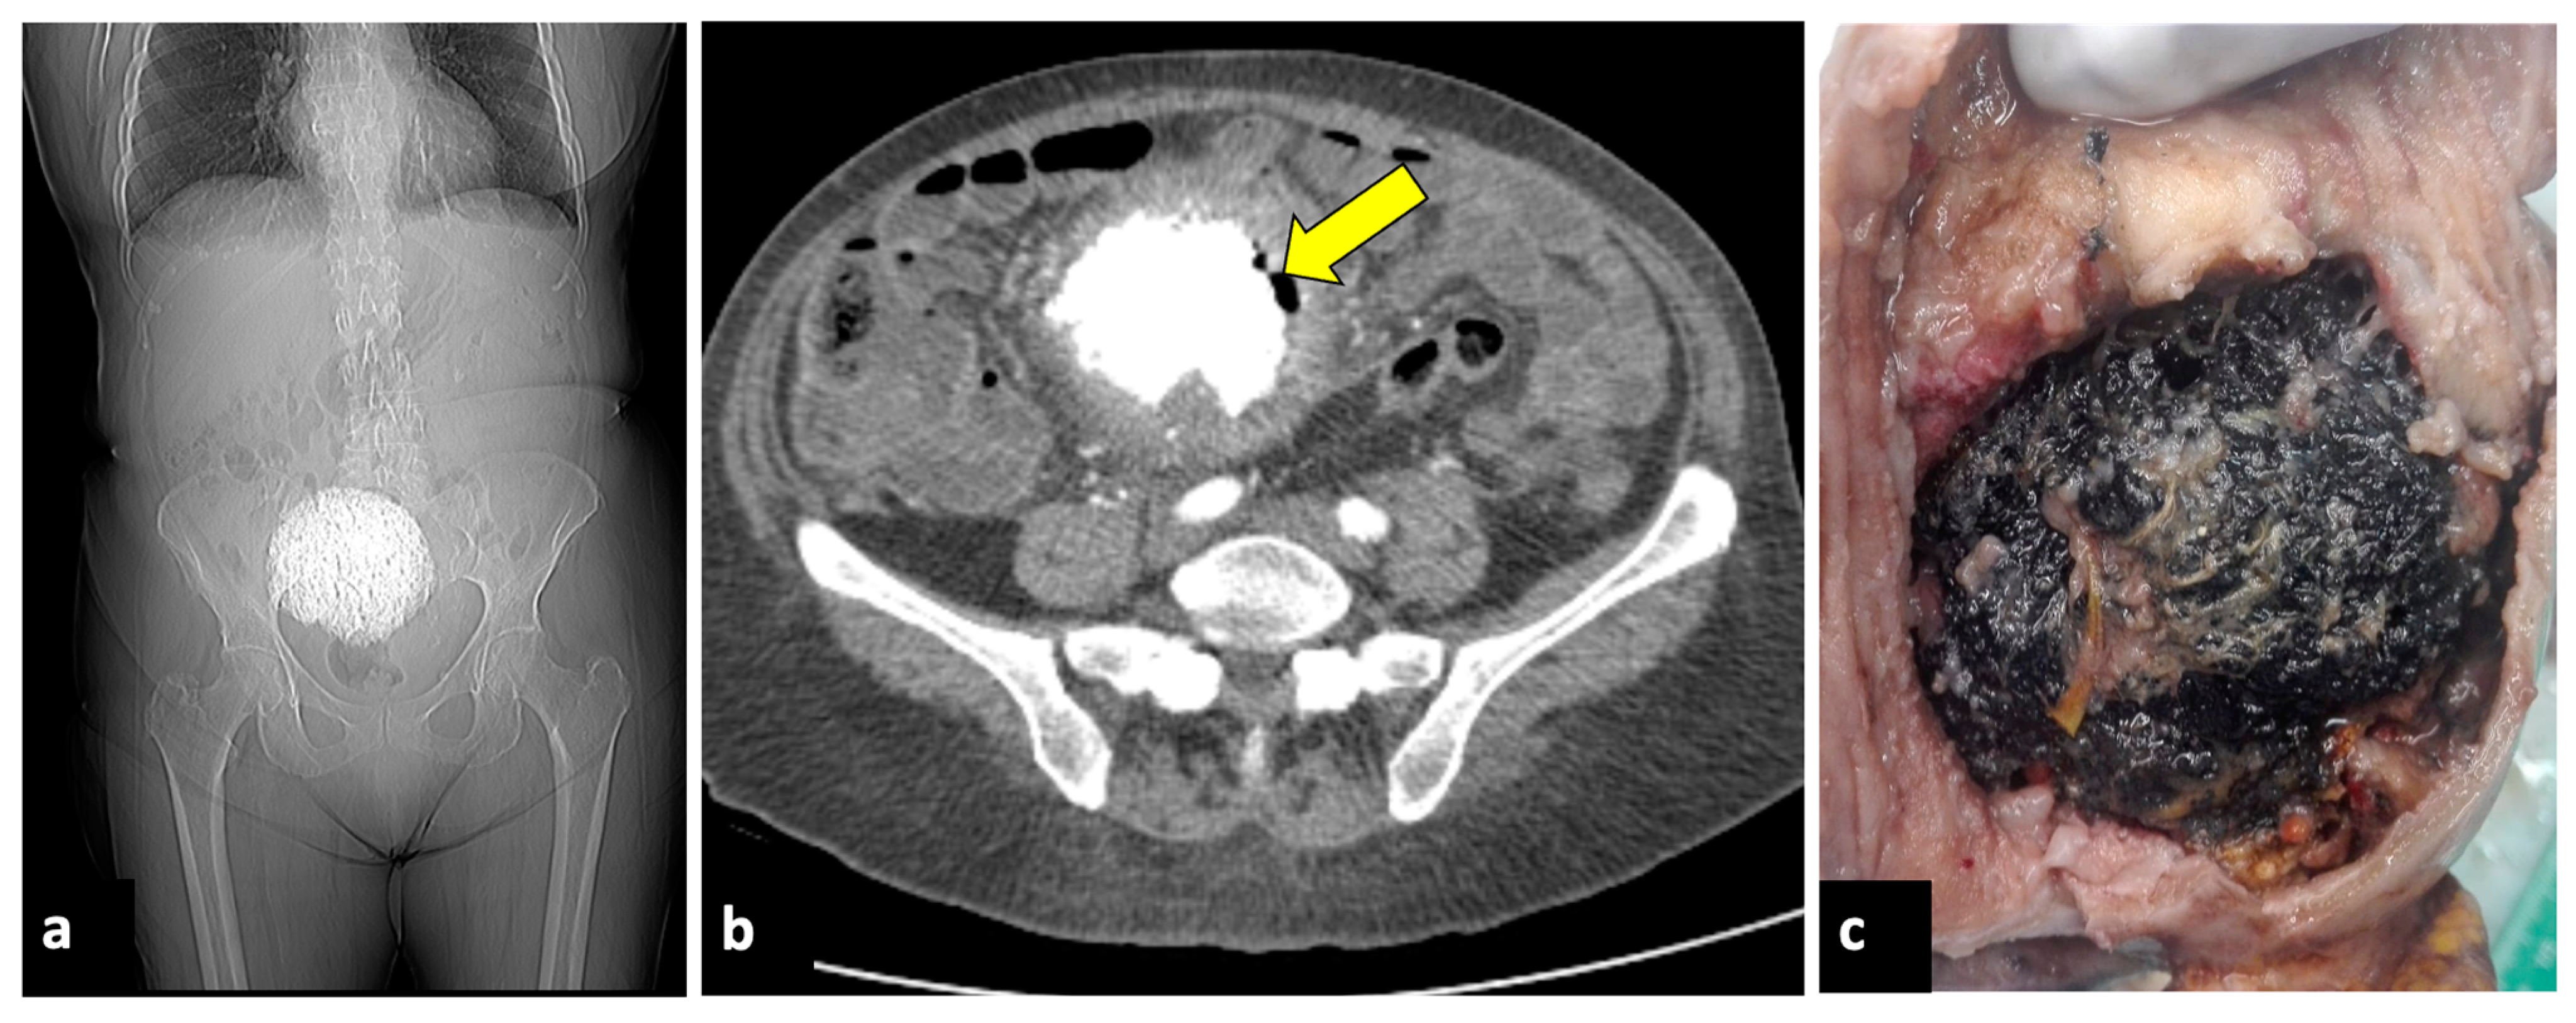

2.6. Complicated Ovarian Teratomas

- Saleh, M.; Bhosale, P.; Menias, C.O.; Ramalingam, P.; Jensen, C.; Iyer, R.; Ganeshan, D. Ovarian Teratomas: Clinical Features, Imaging Findings and Management. Abdom. Radiol. 2021, 46, 2293–2307. [Google Scholar] [CrossRef] [PubMed]

- Park, S.B.; Kim, J.K.; Kim, K.-R.; Cho, K.-S. Imaging Findings of Complications and Unusual Manifestations of Ovarian Teratomas. RadioGraphics 2008, 28, 969–983. [Google Scholar] [CrossRef] [PubMed]

- Mazhoud, I.; Skhiri, W.; Hafsa, C.; Toumi, D.; Maatouk, M.; Ben Salem, A. Ruptured Mature Ovarian Teratoma: A Case Report. Int. J. Surg. Case Rep. 2023, 102, 107788. [Google Scholar] [CrossRef] [PubMed]